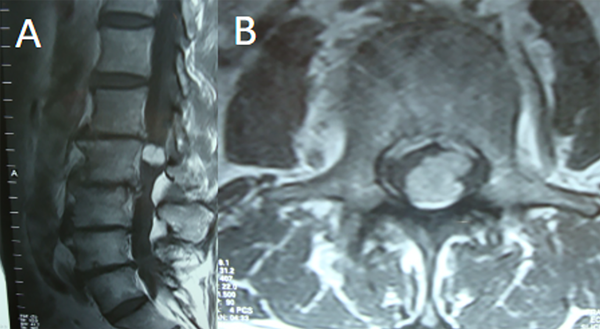

Fig 6. Caso 2. RMN: T1 con contraste sagital (A) y axial (B) que objetiva lesión nodular intradural extramedular L1-L2 a izquierda, con realce homogéneo con contraste.